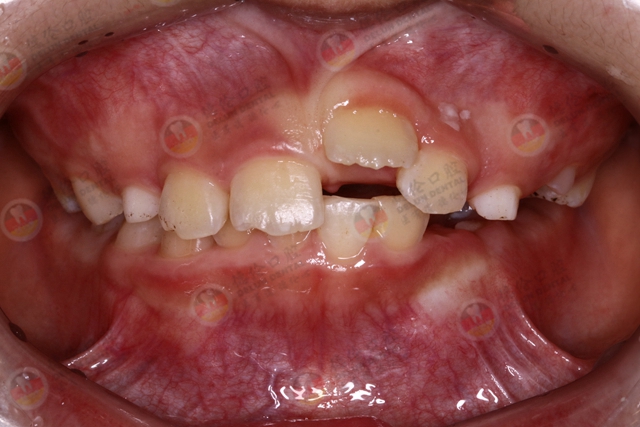

儿童换牙期,乳牙脱落和恒牙萌出关系十分密切。孩子六七岁时,乳牙就已经基本完成使命,自动脱落,随后恒牙逐渐萌出。但是,有些孩子恒牙已经长出来了,而相应的乳牙却迟迟不肯“退位让贤”,恒牙被迫“委曲求全”,从后面萌出,形成一前一后双排牙。在口腔医学中,这种情况被称为乳牙滞留。

“双排牙”一般在七八岁的孩子中常见,通常发生在下牙,也有上牙长双排牙的现象。

双排牙的出现,从临床医学上讲,是由于恒牙顶乳牙的位置发生了偏差。出现双排牙,不及时治疗可诱发其他问题。一般情况下,“双排牙”的危害有以下4点:

01.导致新生恒牙萌出异常,对孩子领骨发育、咀嚼功能、面部美观造成影响。上领的乳牙滞留,有可能会造成反合,也就是俗话说的“地包天”,而下颌常见就是牙齿排列不齐。